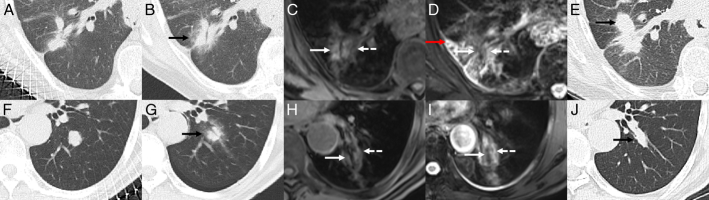

Results: The ablation area of the lesion exhibited central low signal and peripheral high signal on T2WI, central high signal and peripheral equal or high signal on T1WI, and circumferential enhancement in the periphery. The safety margin measured on T2WI was greater than that measured on plain CT and T1WI. On plain CT, the L, S, and V 1 were smaller in the effective treatment group than in the ineffective treatment group ( P <0.05). On T1WI, the V% and safety margin were greater in the effective treatment group than in the ineffective treatment group ( P =0.009 and P =0.016, respectively).

Conclusions: MRI may be a new, valuable method to assess immediate efficacy after MWA for lung malignancies using the ablation zone parameters V% on T1WI and safety margin on T2WI.